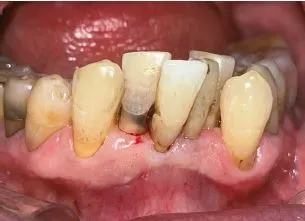

치근면 우식증은 잇몸이 퇴축되어 치근 및 백악질이 노출된 부위, 즉 백악질과 법랑질이 만나는 경계에서 백악질 쪽으로, 퇴축되는 잇몸 경계를 따라 형성된다. (그림 1) 또한 치관에서 발생하는 일반적인 우식과 달리,치근 속의 치수 쪽으로 진행되기 보다 치근면을 감싸며 옆으로 확산되는 경향을 보인다. (그림 2, 3)

치근면 우식증 -3.JPG 그림 3. 치근면 우식증 임상사진